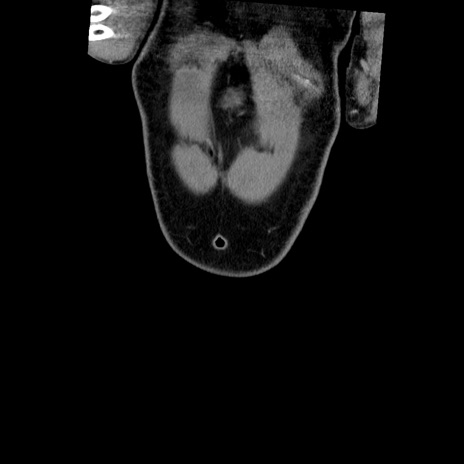

横断像

【症例】50歳代男性

【主訴】腹痛

【現病歴】AVMからの被殻出血のため回復期リハ病棟入院中。 本日午後3時頃急に下腹部痛が出現した。

【既往歴】AVM、被殻出血、虫垂炎、高血圧

【身体所見】意識晴明、左半身不全麻痺、会話の理解は良好、36.5°C、腹部:膨隆、全体に板状硬、下腹部正中に圧痛点あり、反跳痛-、筋性防御不明、右下腹部にope scar

【データ】WBC 9400、CRP 0.06